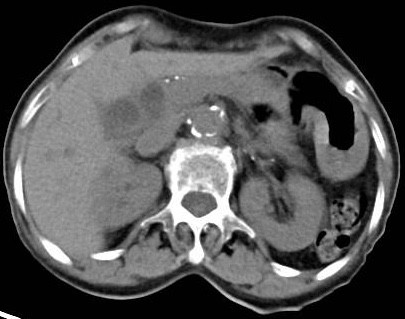

Qua thăm khám và siêu âm bụng, phát hiện bệnh nhân bị áp-xe gan nghi do ký sinh trùng. Các bác sĩ tiến hành chụp CT-Scan ổ bụng, nghi ngờ bệnh nhân có sỏi trong ống mật.

Bệnh nhân được các bác sĩ hội chẩn và quyết định làm nội soi mật tụy ngược dòng lấy sỏi (ERCP). Trong lúc thực hiện ERCP, các bác sĩ phát hiện sán lá gan nhỏ trong ống mật chủ của bệnh nhân.